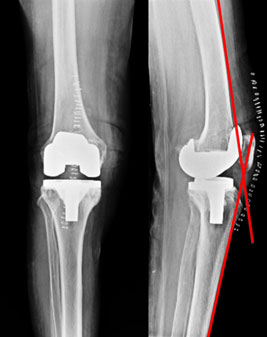

The x-rays after 3 months of surgery. The flexion deformity has resolved. The un-operated side also shows damage, but the patient is not symptomatic on that side so no need for surgery till such time.